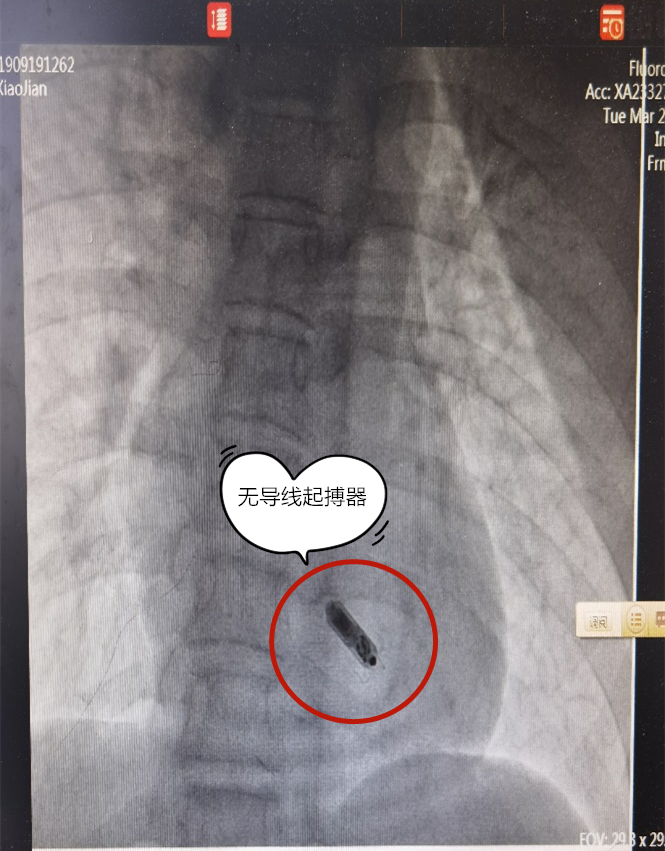

卢孔杰主任带领的起搏团队仔细分析、充分商议后,认为该患者符合无导线起搏器植入 I 类适应症。不同于常规起搏器,无导线起搏器不需要经静脉的导线存在,只需要通过导管微创直接植入右心室,不需要制作囊袋,无伤疤、无凸起,无明显切口,更重要的是术后患者感觉不到自己已经装了起搏器,对以后的生活几乎没有影响。

经过周密的计划与部署,在麻醉科、介入导管室等科室的配合下,卢孔杰主任采取经股静脉通道为患者植入无导线起搏器。然后在术中,又一个难题出现了:患者心腔比较小,可供操作的空间不多,而在心尖部位还发现了类似于心肌致密化不全的表现,这进一步增加了手术的难度。但团队人员都没有放弃,仍旧耐心地寻找着合适的起搏器释放位置。在不懈努力和反复尝试下,终于找到落脚点,释放成功。

无导线起搏器经静脉推送系统进入右室心尖部,是一种没有起搏器电极、无需起搏器囊袋的全新起搏系统,可持续工作 9~13 年。可以提供可靠的起搏、感知,能解决常规起搏系统所带来的挑战:最小化感染、气胸、脱位以及其他和导线及囊袋相关的风险。同时能改善患者的依从性和舒适度,兼容磁共振检查等。患者舒适感强,无疼痛,无切口,基本无出血。